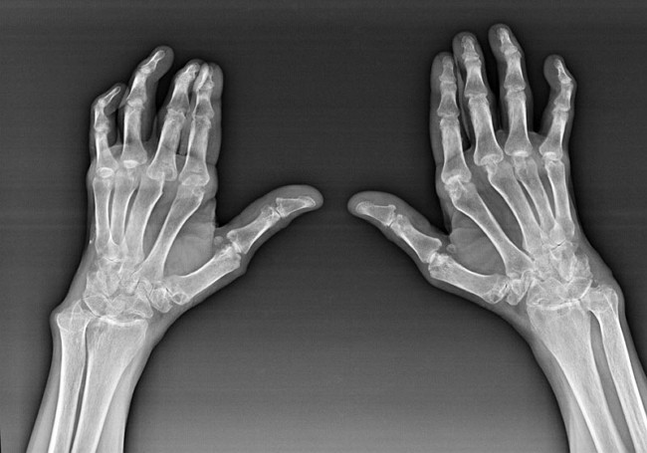

Artrite reumatoide

A artrite reumatoide é unha enfermidade na que o sistema inmunitario humano dana o propio tecido do corpo. Noutras palabras, a artrite reumatoide é unha autoinmunpatoloxía. Esta enfermidade tamén é sistémica porque moitos tecidos están afectados (((Músculos, articulacións, buques, etc.) e órganos (Corazón, riles, pulmóns, etc.) no corpo.

A pesar de que a artrite reumatoide é unha enfermidade sistémica, as articulacións sofren en maior medida, mentres que a lesión doutros tecidos e órganos está nun segundo plano. Con esta enfermidade, case todo tipo de articulacións de cepillos poden verse afectadas (Paredes de brazos, camiños carpianos, metacarpal-falanx, articulacións interpalánxes). A lesión adoita ser simétrica (isto. As mesmas conexións están afectadas) Dor nas articulacións danadas, acompañadas de inchazo. Pola mañá, mentres se levanta da cama, hai unha certa rixidez nas articulacións afectadas, que duran aproximadamente 1 hora e pode desaparecer sen rastro.

Moi a miúdo con artrite reumática preto das articulacións afectadas do cepillo (Máis a miúdo as articulacións da interfalanx de piano-falanx) Aparecen reumatoides. Son unha formación redondeada que está baixo a pel. Estas formacións son máis comúns na parte traseira no cepillo. Con palpación son axustados, inactivos e indoloros. O número deles pode variar.